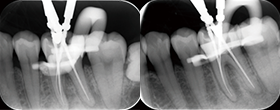

Case2 直線根管

• CC「左下奥違和感」主訴に来院

左下6遠心根に透過像認める

• インレー除去

透過像に一致した部位にサイナストラクト認める

• コンポジットレジンにて隔壁作成

• 作業長確認

最終拡大#30/.04テーパー